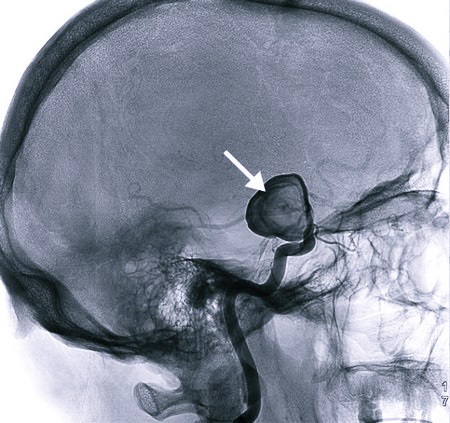

Субарахноидальное кровотечение происходит спонтанно, в 50% случаев причина – разрыв артериальной аневризмы. Высокое АД провоцирует 30% подобных приступов. Третий источник возникновения апоплексического удара – черепно-мозговая травма. В остальных случаях (7–10%) – иные факторы: опухоль, патология сосудов спинного мозга и др.

Как происходит субарахноидальный инсульт головного мозга? При кровоизлиянии кровь попадает под паутинную оболочку и заполняет базальные цистерны, борозды полушарий. ОНМК бывает очаговым либо общемозговым, охватывающим все пространство. Происходит спазм сосудов, который нарастает постепенно. Больным на 3–4 сутки становиться хуже.

Справка: Аневризма – расширение просвета аорты, с выпячиванием (образование кисты) стенки сосуда, наполненного кровью. В результате растяжения трехслойное строение тканей истончается, остается только слой соединительной ткани. Под давлением кровотока сосудистая стенка не выдерживает и лопается.